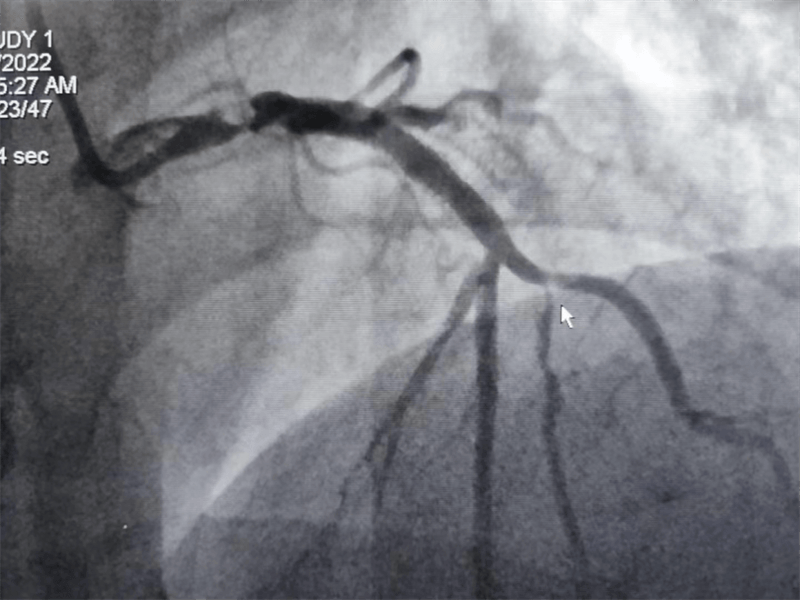

冠脈造影結果提示:左主干末端及前降支開口處99%狹窄,回旋支開口處80-90%狹窄,中段支架內100%閉塞。看到造影結果時,在場醫護人員無不驚出一身冷汗:左主干病變“細”如發絲——生死一線牽!患者拒絕搭橋手術,所以選擇介入處理該病變。

我們結合患者病變特點,對回旋支支架內閉塞病變處藥物球囊治療,左主干病變植入1枚支架,術后,造影顯示左主干病變處支架植入狀態良好,血管內超聲顯示支架貼壁良好,患者血壓、心率穩定,癥狀完全緩解,并安全返回重癥監護室進一步治療,術后張大伯無明顯不適,生命體征穩定,病情明顯好轉。